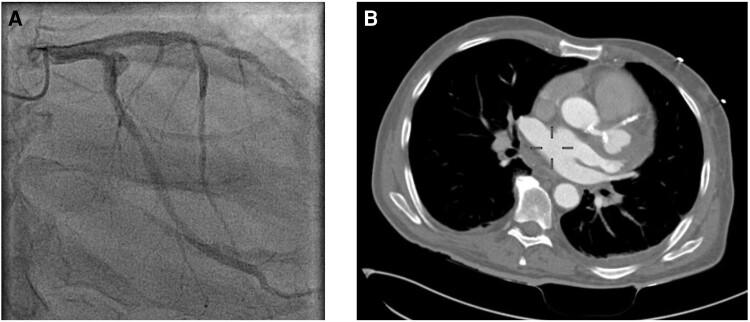

Here, we present a case of a 55-year-old patient, who developed a PSA of the proximal left circumflex artery after stent implantation of the left main artery, left anterior descending artery, and left circumflex artery. Within <1 year, the patient was readmitted to different hospitals due to cardiac decompensation and myocardial infarction. Thereafter, coronary angiography and computed tomography scans were performed, and progression of the PSA could be documented. Interventional therapy was chosen due to the high surgical risk of the patient. Implantation of a covered stent from the left main artery into the left anterior descending artery was chosen to treat the PSA, thereby silencing the chronically occluded left circumflex artery, followed by dilatation with a non-compliant balloon. The patient has remained asymptomatic in a 6-month follow-up.

在此,我们报告1例55岁患者,其在左主干、左前降支及左旋支植入支架后发生左旋支近端PSA。在1年内,该患者因心功能不全和心肌梗死再次入住不同医院。此后,进行了冠状动脉造影和计算机断层扫描,可记录到PSA进展。由于患者手术风险高,选择了介入治疗。选择从左主干至左前降支植入覆膜支架治疗PSA,从而使慢性闭塞的左旋支不再显影,随后用非顺应性球囊进行扩张。在6个月的随访中,患者一直无症状。